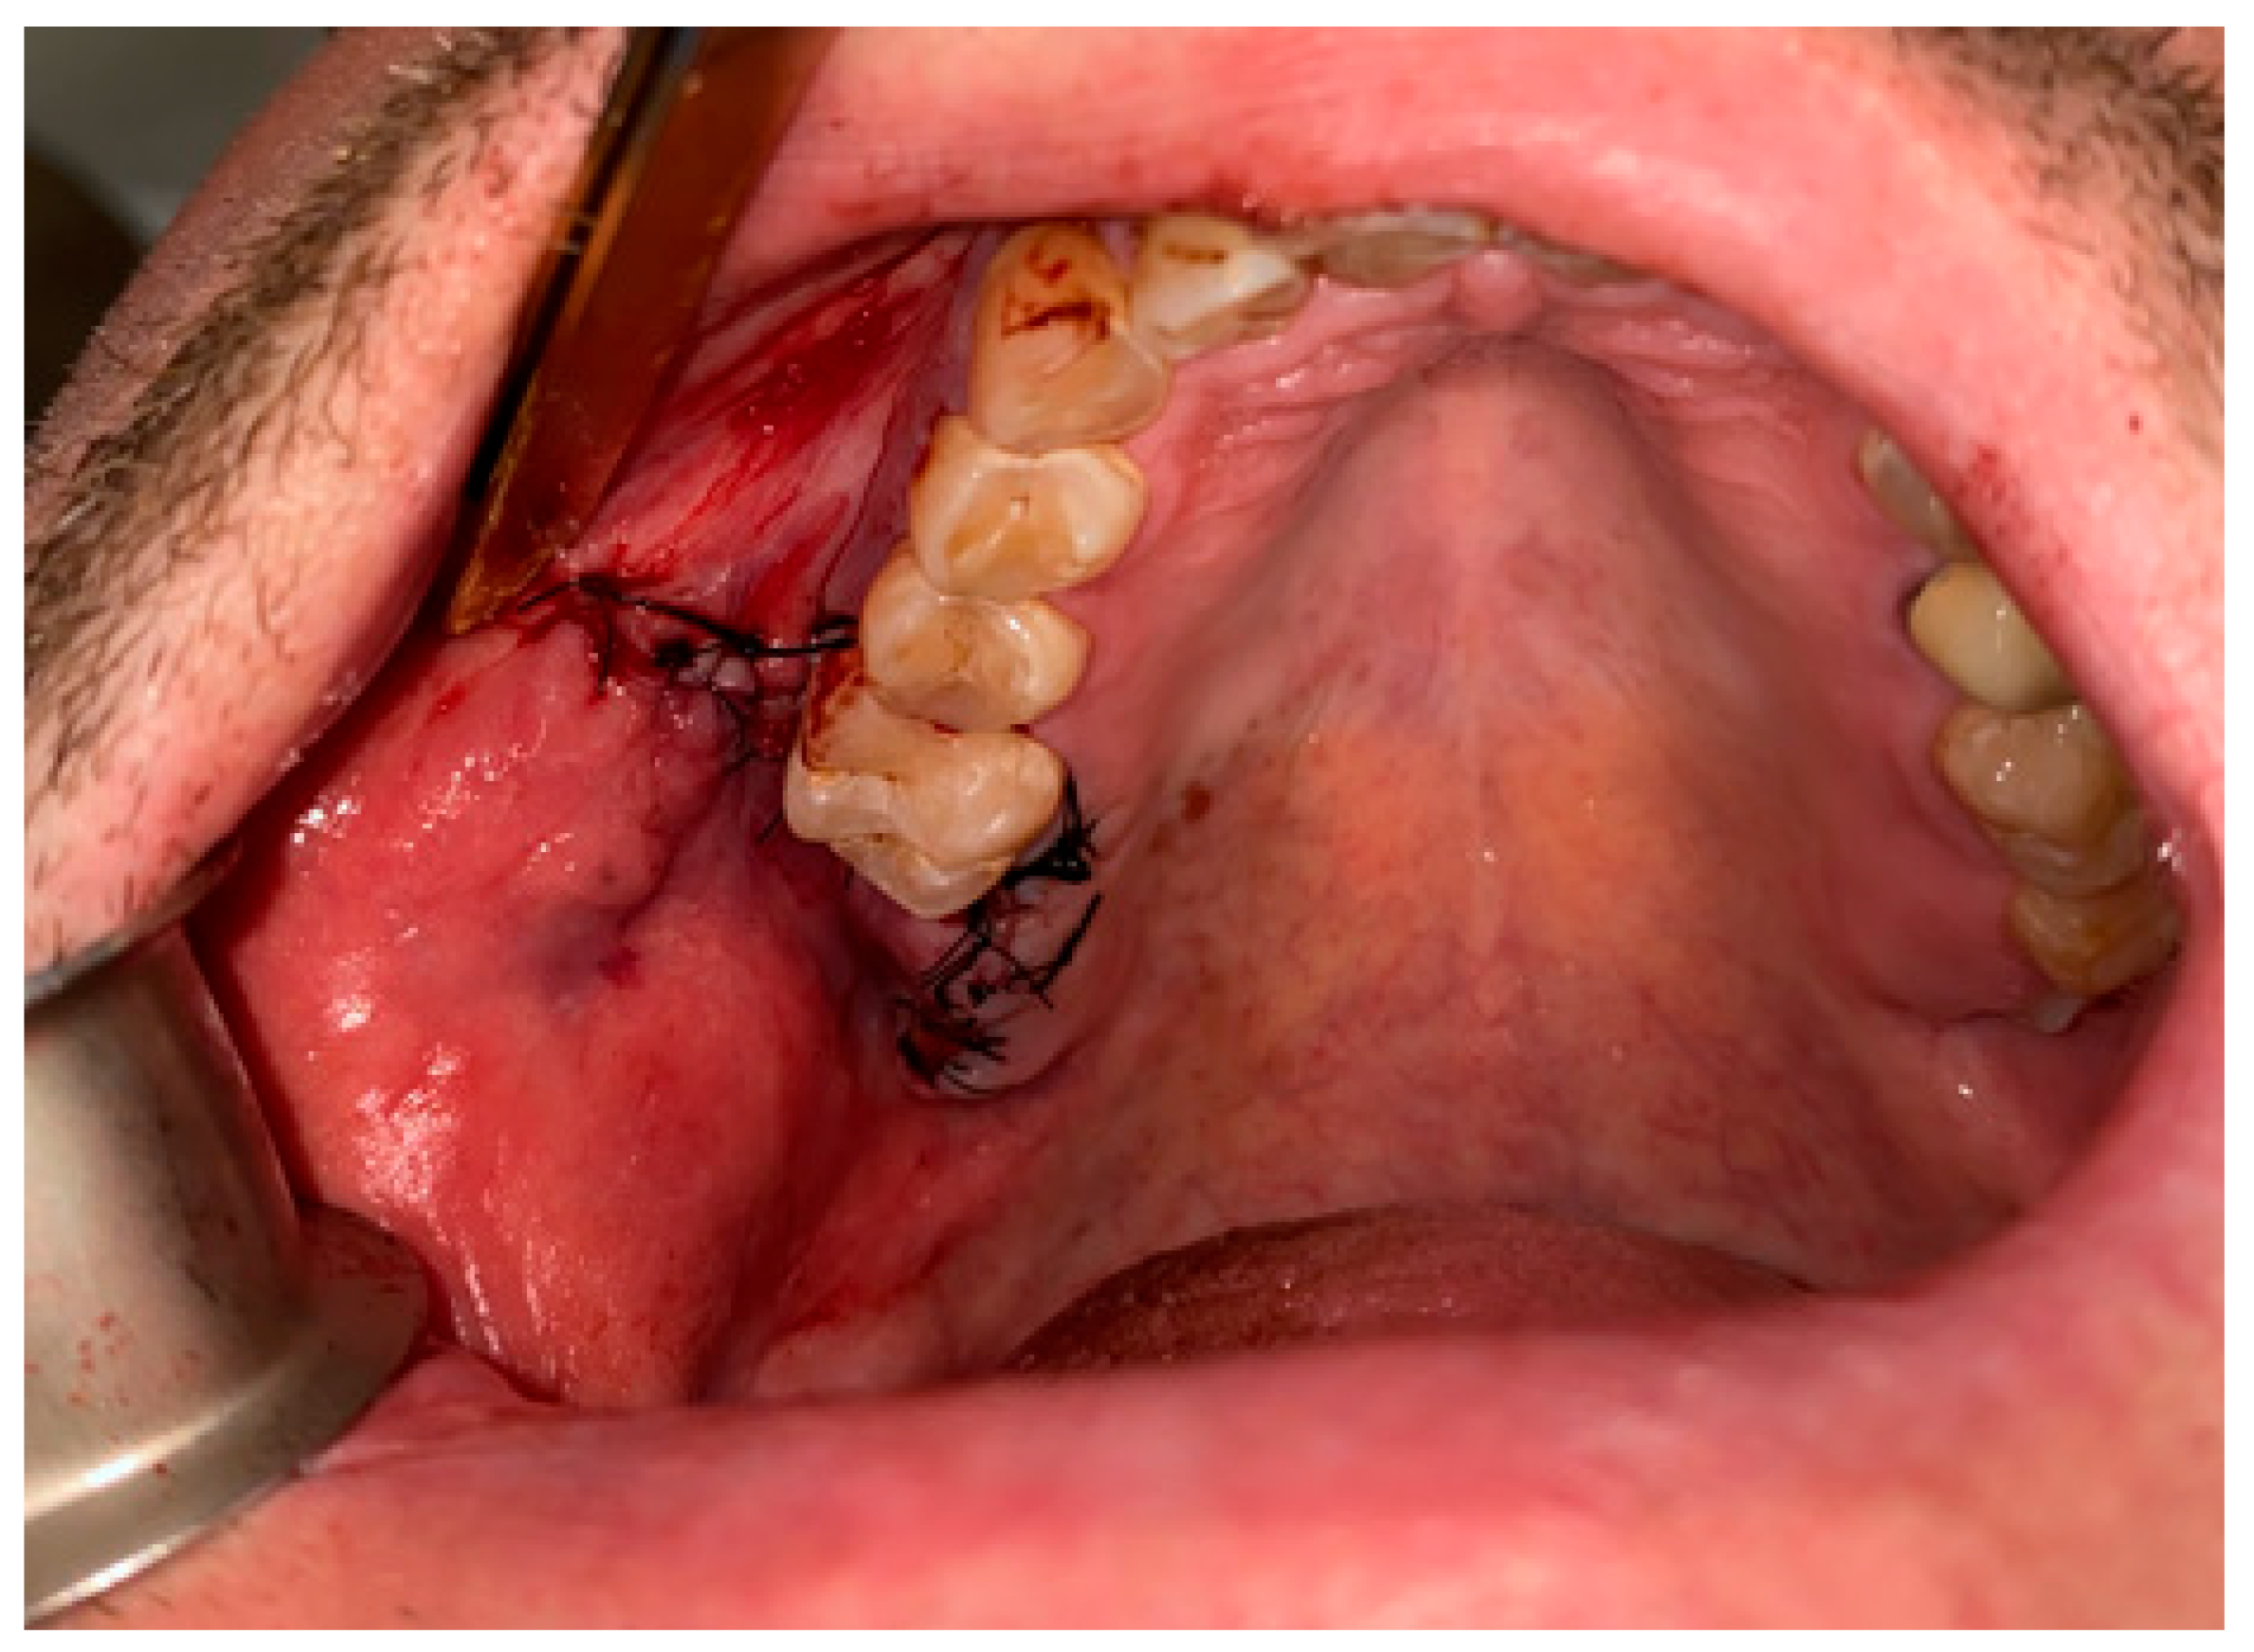

Figure 8. Proper suturing of bone defect and closure of the communication between the oral cavity and right maxillary sinus.

Figure 4. A very good result with limited buccal corridor narrowing and good tissue volume at the top of the dental arch.